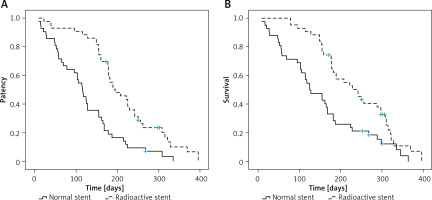

Stent patency

Similar re-stenosis rates were found in the normal and radioactive stent insertion groups (26.2% vs. 23.2%, p = 0.754, Table II). All patients in the normal stenting group who experienced r-stenosis were treated via biliary drainage catheter placement, while 9/10 patients with re-stenosis in the radioactive stent group also underwent biliary drainage catheter placement. The remaining patient had originally undergone unilateral radioactive stent insertion and was therefore treated by placing a second stent from the contralateral intrahepatic biliary tract.

Radioactive stent insertion was associated with significant prolongation of stent patency relative to the normal stent group (195 days vs. 115 days, p < 0.001, Figure 2 A). Cox regression analyses revealed that factors related to increased stent patency included Bismuth III HC (p = 0.027) and radioactive stent use (p = 0.018) (Table III).

OS

Following stent placement, a transarterial chemo-infusion was conducted in 14 and 12 patients in the normal and radioactive groups. Postoperative chemotherapeutic treatment was based on each patient’s condition and approval. During the follow-up period, 39 and 37 patients in these two groups died, with 65 patients succumbing to tumor progression, 8 to severe abdominal infection, and 3 to acute renal failure.

Individuals who underwent radioactive stent insertion survived significantly longer than those who underwent normal stenting (242 days vs. 125 days, p = 0.002, Figure 2 B). Higher ECOG PS (p = 0.043), post-operative TBIL (p = 0.014), radioactive stent use (p < 0.001), and postoperative chemotherapy use (p = 0.003) were all associated with longer OS according to Cox regression analyses (Table IV).

Here, the insertion of radioactive stents did not contribute to any significant reduction in the rate of re-stenosis, although it was associated with significant prolongation of stent patency. Strikingly, radioactive stenting was associated with more prolonged patient OS. Since radioactive stent insertion was predictive of both longer stent patency and OS, and postoperative chemotherapy was also predictive of prolonged OS, chemotherapy may represent a practical option for the simultaneous adjuvant treatment of HC patients undergoing radioactive stent insertion.